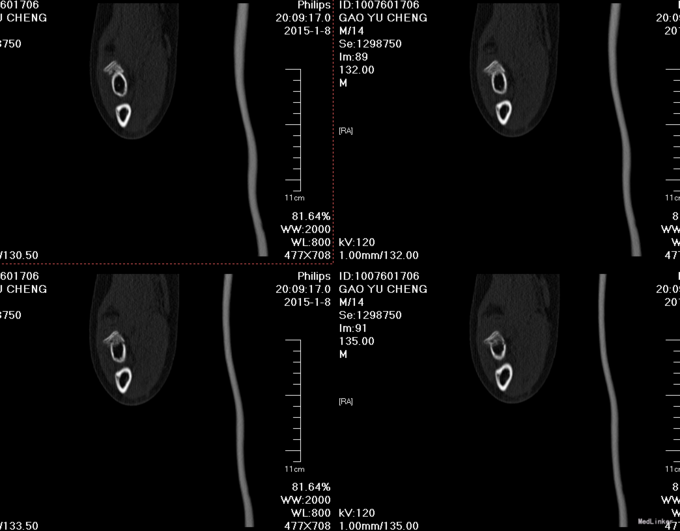

患者自述于2015年1月8日14时余不慎摔伤,右手伸直着地,感觉疼痛、肿胀,活动受限。遂急诊来我院,急诊给予行右肘关节三维CT检查,提示:右桡骨近端骨折。现为求进一步系统治疗送入我科,急诊以“右桡骨颈骨折”为主要诊断收入我科

专科查体:患者无明显外伤伤口,肘关节肿胀,右尺骨鹰嘴压痛(+),右桡骨小头处深压痛(+),肘关节活动受限,右上肢皮肤感觉无减退,桡动脉可扪及搏动,皮温正常,拇指背伸肌力正常。 辅助检查:我院右肘关节三维CT: 右桡骨近端骨折